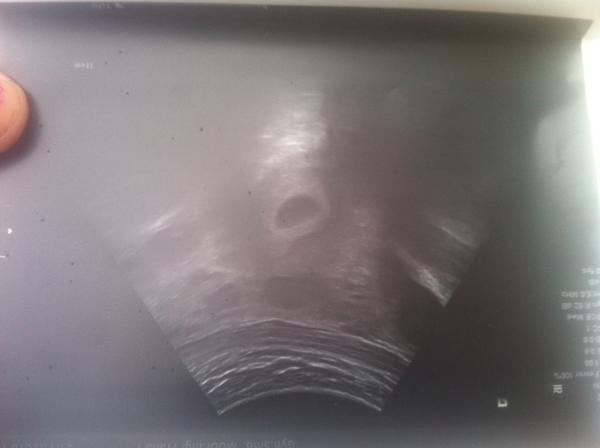

@nikinu jsen tehotna ve 4 tydnu 🙂

@katule22 tehotna ve 4 tydnu byka jsem na gynekologie

@sandraaberuska a to na gynekologii něco viděl?

@lachtanice86 ano videl